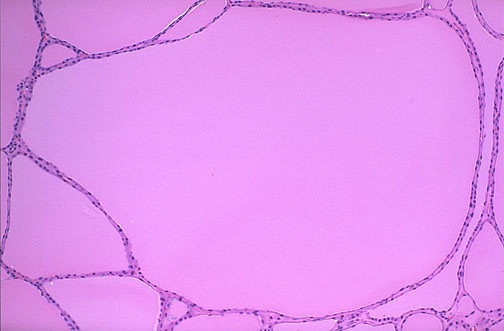

- Figure 5: Histopathologic examination of the mass, using hematoxylin-eosin revealed multinodular goiter (irregularly enlarged follicles with flattened epithelium consistent with inactivity).